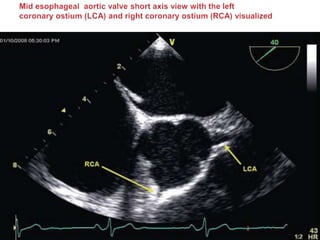

 The coronary ostia are well seen in the mid esophageal AV short

(left [LCA] and right [RCA]) and AV long (RCA) axis views.

 In the SAX view the left main stem (LMS) and proximal portion of